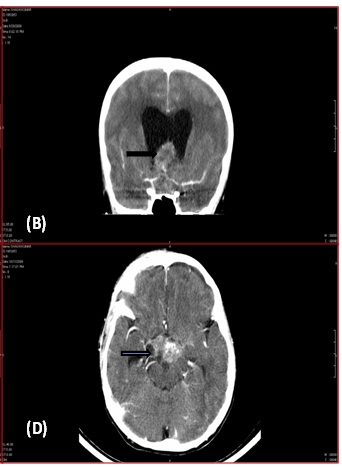

Preoperative CT Scan showed extra-axial enhancing lesion (3.3X2.5X3.7cms) [Table/Fig-1a,b] in sellar region causing obstruction of suprasellar (intra-peduncular cistern) along with a hyper dense area in periphery of lesion with dilatation of frontal/ temporal/ occipital horns of lateral ventricle. Fourth ventricle appeared normal [Table/Fig-1c,d].

Pre- operative CT Scan showing extra-axial enhancing lesion.

CT Scan showing recurrent lesion (after 3 months of complete surgical clearance)

Three months later, the child presented with nocturnal urinary incontinence and difficulty in walking. CT scan [Table/Fig-1c&d] showed a lesion in suprasellar region with evidence of hydrocephalus. Histopathological examination of excised lesion showed tumour recurrence. Patient was advised Radiotherapy and further follow up.